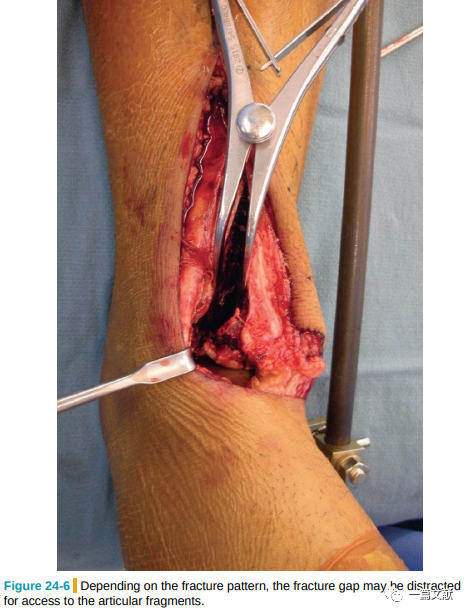

在胫骨前肌腱内侧缘切开深筋膜和骨膜,行骨膜下分离,注意不要损伤胫前肌腱鞘,牵开整个全厚皮瓣,以便术后缝合。注意避开内侧的大隐静脉和神经,必要时向内侧牵开。如下图: